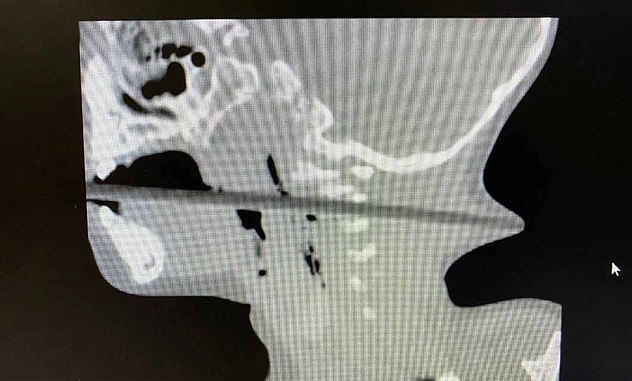

به گفته پزشکان چینی گلوی "لین لین" در پی این حادثه به شدت آسیب دیده است وهنگامی که مادرش او را به بیمارستان منتقل کرد پزشکان بخشی از چوب را پشت گردنش مشاهده کردند.

پزشکان چینی دست به کار شده و بلافاصله "لین لین " را تحت عمل جراحی قرار می دهند. به گفته یکی از پزشکان بیمارستان "لین لین" بسیار خوش شانس بوده که از این حادثه جان سالم بدر برده است زیرا این میله چوبی می توانست صدمات جبران ناپذیری به کودک وارد کند.